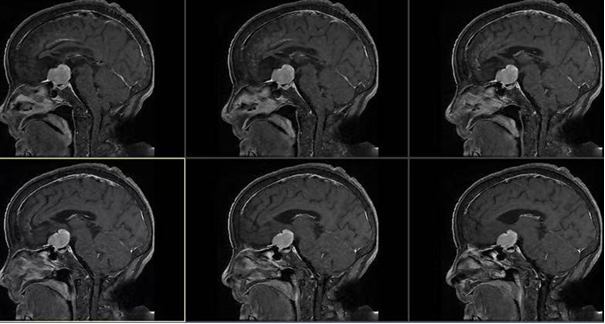

如果说潘先生的案例是闪电战,那么83岁陈奶奶的经历则是一场攻坚战。老人两年多来视物模糊,近期加重至无法独立行走。检查发现,鞍区有一枚脑膜瘤,紧紧压迫视交叉。高龄、心肺功能减退、鼻腔解剖变异……每一个因素都让常规手术风险倍增。

兰小磊团队再次把目光投向经眶入路。这个通过眶上或眶外侧微小切口建立通道的技术,既能避开开颅大范围暴露,又可避免对鼻腔结构的干扰。在多学科协作保驾护航下,手术如期进行。内镜下,肿瘤与视神经、颈内动脉界限清晰,兰小磊沉稳地分块切除病变,重要结构毫发无损。术后第一天,陈奶奶惊喜地发现“眼前亮堂了”;第三天,她已能在搀扶下行走。“这么大年纪还能做手术,而且恢复这么快,真是没想到!”家属的感激之情溢于言表。